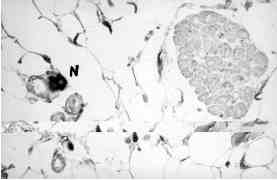

Figura 4: Confirmación de las fibras nerviosas (N), mediante la técnica inmunohistoquímica con anticuerpos contra la proteína S-100